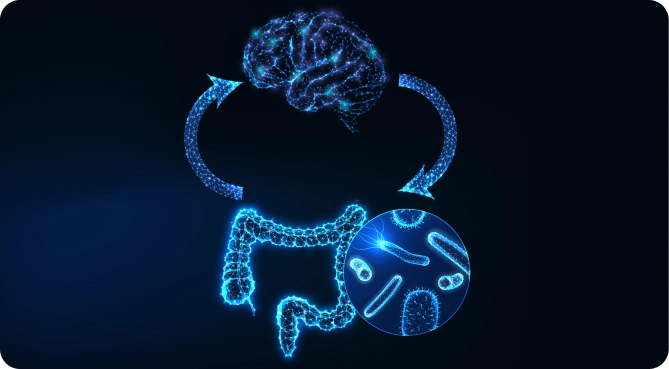

She focused on healing his body, beginning with his gut.

The boy’s diet was gently shifted to include more nutrient-dense foods, giving his body the tools it needed to rejuvenate.

Then, the doctor ran specialized tests to evaluate the boy’s gut health.

What she found was shocking but not uncommon in children with autism: a hidden yeast infection and small intestinal bacterial overgrowth (SIBO) were wreaking havoc on his system.

Dr. Moldenhauer said, “Healing up the gut was magical.

It was clear: this little boy was showing symptoms of autism because of what was going on deep inside his body.

He wasn’t in need of more medication, but of investigating the root cause.

Once the doctor addressed the underlying causes holistically, this boy’s life changed forever.

- The Forgotten Factor: Discover the powerful connection between your child's gut, immune system, anxiety, and ADHD - and how addressing this link can support symptom improvement